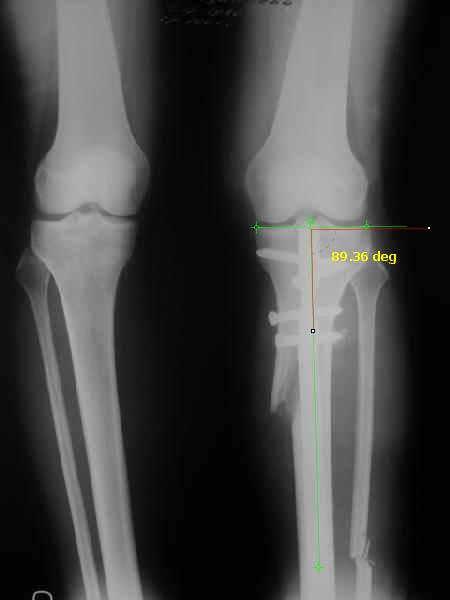

Вот ещё картинки, которые отправлял в Ортопод. Коррекция кривизны и удлинение на 3 см.

Yesterday one leg was done (my plan to make both in one session were cancelled because of external reasons). So much exciting and useful experience.

The osteotomy line i planned to make a bit oblique, but not so as you suggested. But at the moment of osteoclasis after corticotomy through the anterior stab wound the line became almost as you described. Now problem is how to reproduce thee line at the next leg ;-)

The prominent fragment seems to be useful for cosmetic purposes, because aesthetic guys perform medialization of the distal fragment to gain attractive curve at the medial side of the leg. Also all locking options became available - initially i planned to engage only two most

proximal 45 degree holes.

I cut the fibula because i externally rotated the distal fragment by 6-7 degrees. With only angular correction it didn't show any displacement.

Today CT for estimation of rotation was performed, results i will see only tomorrow. Rotation of the operated limb can be corrected with the second surgery. Comments/critics are welcome.

См. снимки. Пока очевидно, что анатомическая ось большеберцовой кости заняла положение под прямым углом к проксимальной суставной площадке. Что можно расценить как 2-3 градуса гипервальгуса. А можно и считать в пределах нормы (85-90 градусов)...

АЕ> И где после операции располагается надколенник?

Где и был. Остеотомия подбугорковая.

Снимки в приложении - фас сравнительный с неоперированной ногой. Жду критики.

Впрос про остеотомию большеберцовой непраздный. Эта получилась при надломе несколько более наклонно, чем я делал (сейчас проблема,

как на второй ноге сделать так же). Вот этот высоящий "зуб" центрального отломка не заменит ли в плане косметики то, что получается при медиализации дистального?

Nice job!

It is very interesting to me that as you have derotated the tibia you have centred the patella, I think and the prox tibia looks much more anatomic.

The analysis in the attached images is direct, just using the tools.

Tibial tilt is perhaps more than you want but the tibial correction is to 90 (very slight over

correction.

Will need full length views to tell us about the hka but it appears neutral.

Measurements took 4 mins